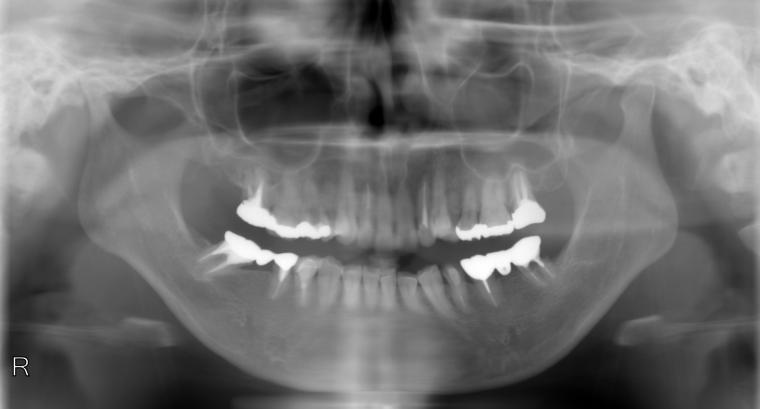

BEFORE

36歳女性/下2本欠損/インプラント埋込手術

左下のブリッジが割れそうでご来院の患者さんです。

保存状態が厳しかった為、第一大臼歯と第二大臼歯が抜歯となりました。

第一大臼歯と第二大臼歯をインプラント、第二小臼歯をクラウンでの治療を希望されました。